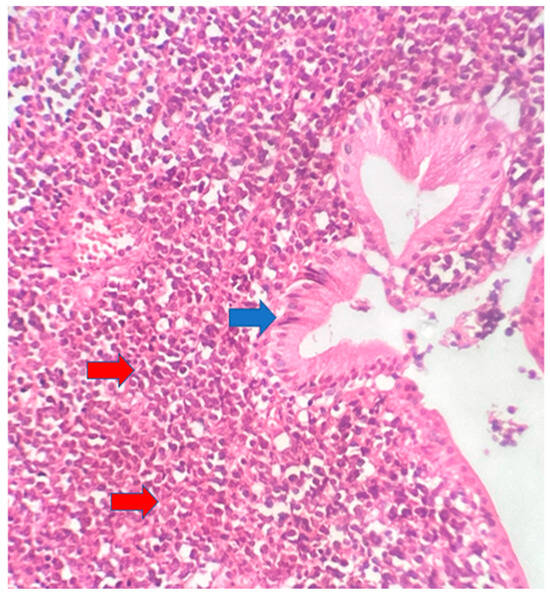

The postoperative histopathological examination of the resected specimen occurred on 07/16/99 at the Department of Pathology of Clementino Fraga Filho University Hospital (HUCFF/UFRJ). The macroscopic examination showed a gallbladder measuring 4 cm × 1.0 cm × 0.9 cm. The serosa was opaque, and the wall thickened and became white, with a firm consistency. The specimen was re-evaluated by a hematopathologist on 08/19/22 (C.B.M), who confirmed the diagnosis of BL through microscopic analysis and immunohistochemical study according to WHO, 2022 [13]. Morphological analysis revealed diffuse proliferation of intermediate-sized cells, with small nucleoli invading and destroying the bladder wall, with a high apoptotic and mitotic index. The neoplastic cells showed positivity for CD20, CD10, Ki67 99%, and EBER by in situ hybridization (EBER1) [13,14]. Combined with the patient’s medical history, the final diagnosis was gallbladder BL. This is an AIDS-defining malignancy (ADM), codified as 2A85.6 (BL) according to ICD-11 MMS [15]. There are five photographs of the sample in question below (Figure 1, Figure 2, Figure 3, Figure 4 and Figure 5).

Figure 1. Gallbladder BL. Neoplasm consisting of intermediate-sized cells (red arrows) located in the gallbladder chorion (blue arrow). 10× magnification.